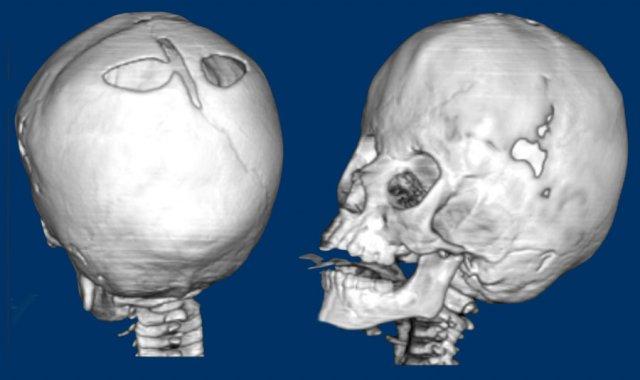

Hình ảnh

Hội chứng Saethre-Chotzen. Ở trẻ hai tháng tuổi, có hình ảnh dính khớp vành hai bên với hình dạng hộp sọ biến dạng nặng nề. Thóp được mở rộng đáng kể.

Cùng bệnh nhân như trên.

Ở ba tuổi, có hình ảnh đầu nhỏ do tình trạng gần như dính toàn bộ khớp sọ.

Lưu ý hình ảnh lỗ đỉnh hai bên giãn rộng.

Trẻ ba tháng tuổi mắc hội chứng Pfeiffer.

Có hình ảnh dính khớp vành hai bên với thóp trước và thóp chũm giãn rộng.

Sự phồng ra ở vùng thái dương tạo nên hình ảnh ba thùy, còn được gọi là ‘dị dạng đầu lá cỏ ba lá’.

Lưu ý hình ảnh giãn não thất kèm phù quanh não thất.